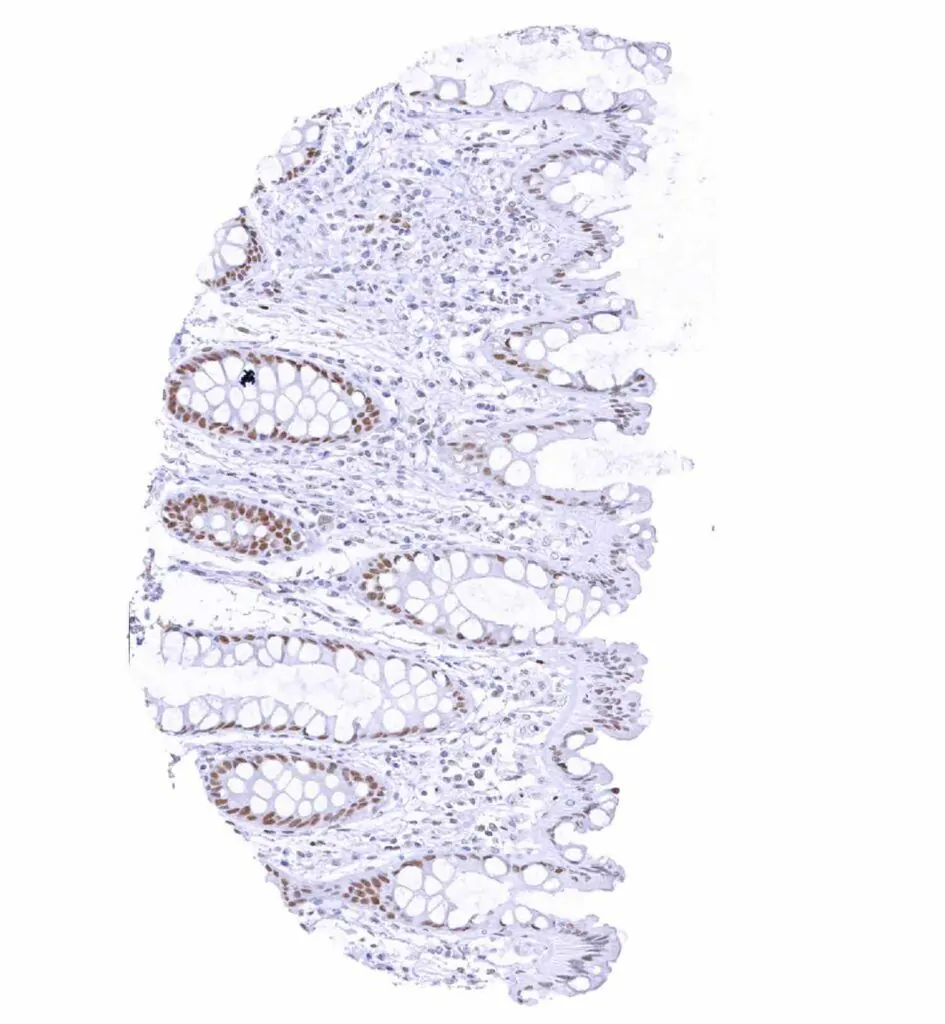

Rectum, mucosa – Weak to moderate TLE1 staining in epithelial cells. Staining is stronger in crypts than at the surface